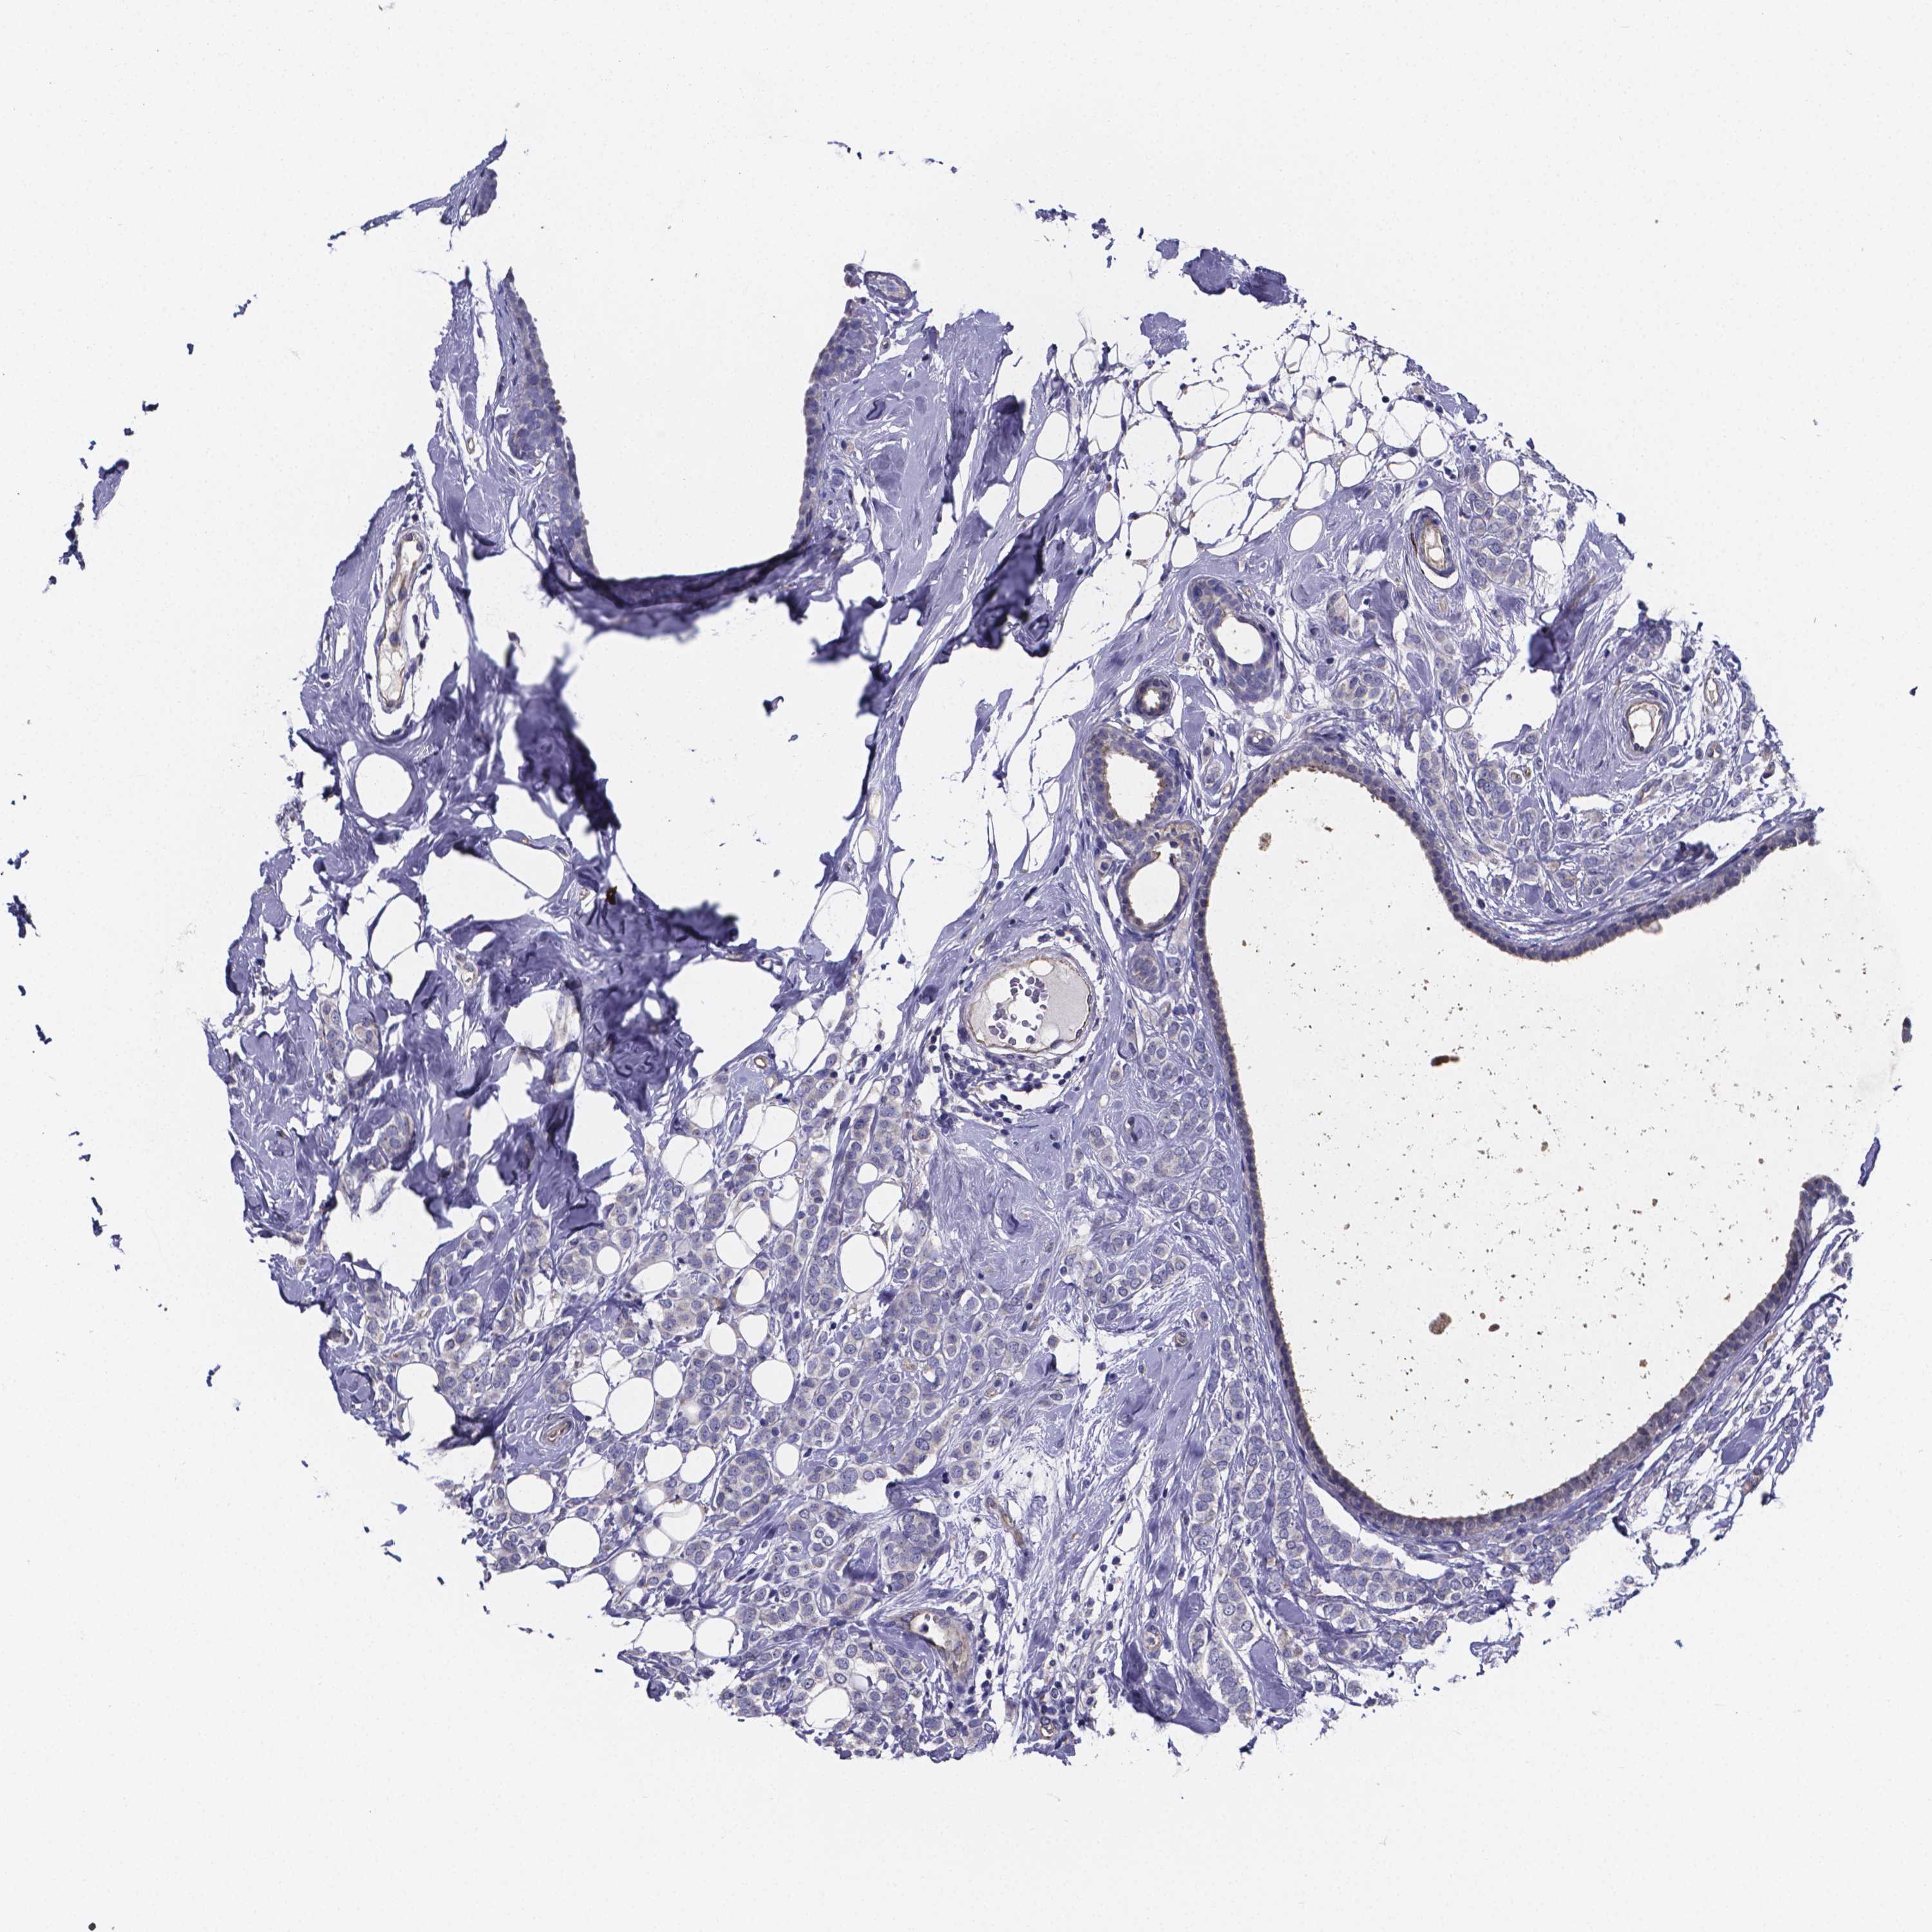

BRCA TCGA BRCA VALIDATION PROTEIN EXPRESSION